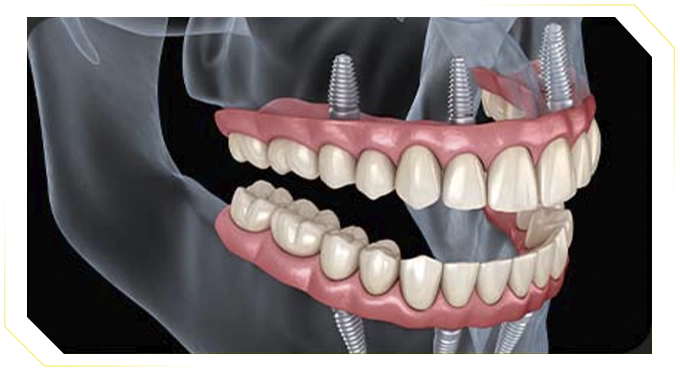

O que é a prótese protocolo?

A prótese protocolo é uma solução moderna e fixa para quem perdeu todos os dentes de uma arcada (superior ou inferior). Ao contrário das dentaduras comuns que podem sair do lugar, a prótese protocolo é fixada com parafusos sobre implantes dentários — trazendo mais segurança, conforto e estética.

Veja como funciona

Entenda a tecnologia por trás da nossa inovadora prótese protocolo

Estrutura

Suportes ou estruturas de metal, normalmente de titânio, posicionados cirurgicamente para substituir as raízes dentárias.

Prótese

Implantes dentários (normalmente de 4 a 6) são colocados no osso da mandíbula ou maxila. Sobre esses implantes, é parafusada uma prótese com todos os dentes da arcada.

Reabilitação

Prótese fixada ao implante com parafusos, só removida pelo dentista. Quando há o travamento adequado (carga imediata), o paciente pode ser reabilitado em até 3 dias. O resultado é uma prótese firme, natural e funcional, que não sai da boca.